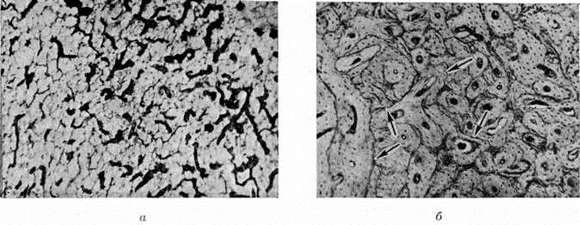

В результате костное вещество убывает, что выражается в остеопорозе (смотри полный свод знаний). В других — зрелая костная ткань в значительной мере замещается незрелым патологический костным веществом — остеоидом, например, при рахите, или в связи с ускорением темпов перестройки новые костные структуры имеют примитивное строение (рисунок 1, а), что характерно для паратиреоидной Остеодистрофия Иногда вновь образованная костная ткань выглядит относительно зрелой, но в связи с ускорением темпов рассасывания и созидания в костном веществе появляется большое число линий резорбции, а также «обломочных» структур в виде островков старых костных пластин среди новообразованной костной ткани. Реже Остеодистрофия выражается в усилении костеобразовательных процессов, в результате чего развивается остеосклероз (смотри полный свод знаний), например, в некоторых случаях почечной Остеодистрофия Присутствующая в костях кроветворная ткань замещается волокнистой соединительной, нередко остеобластической, тканью (рисунок 1, б). При резко выраженных трофических сдвигах, например, при паратиреоидной Остеодистрофия, костных кистах, спонтанном массивном остеолизе, появляются большие очаги деструкции костей, даже исчезновение целых сегментов. Исчезнувшие костные структуры замещаются волокнистой соединительной тканью. При резком ускорении темпа рассасывания костные структуры не успевают формироваться и в костях появляются очаги деструкции с опухолевидным разрастанием костеобразующей мезенхимы — «бурые опухоли» (рисунок 1, в). Местной Остеодистрофия, помимо выделенной А. В. Русакович ангионевротической Остеодистрофия, можно считать морфологический изменения, которые возникают при некоторых статических нарушениях. Например, при таких деформациях, как genu valgum или genu varum, Hallux valgus (смотри полный свод знаний), болезнь Бланта (смотри полный свод знаний Бланта болезнь) и другие, в области поражения кости обнаруживаются морфологический признаки Остеодистрофия: очаги перестройки, умеренно выраженная атрофия кости или остеопороз, частичное замещение кроветворной ткани волокнистой соединительной. Кроме того, морфологически к Остеодистрофия можно отнести обширную группу заболеваний, называемых остеохондропатиями (смотри полный свод знаний). Как было показано рядом исследователей, в том числе Аксхаузеном (G. Axhausen, 1923), в связи с местным нарушением кровообращения кость теряет свои механические свойства. Остео дистрофические изменения развиваются также в результате травмы или перегрузки кости. Подобные же изменения в связи с перераспределением регионарного кровообращения (рисунок 2, а) и интенсивной перестройкой костной ткани (рисунок 2, б) наблюдают при перегрузках костей одной нижней конечности при длительном выпадении функции другой, при перегрузках неокрепшей костной мозоли. часть о., остеохондропатии и близкие к ним изменения в свете современный представлений о дистрофии и нарушениях микроциркуляции вернее называть не асептическими некрозами, а Остеодистрофия дисциркуляторного типа. Токсические остеодистрофии. Генерализованные формы Остеодистрофия нередко возникают при длительном воздействии токсических веществ — фтористых соединений (так называемый криолитовая болезнь), препаратов мышьяка, ртути, свинца, избыточного введения железа — уровская болезнь (смотри полный свод знаний Кашина—Бека болезнь). Эта форма Остеодистрофия встречается также у детей грудного возраста при хронический отравлении матери свинцом: выделяясь с грудным молоком и попадая в организм ребёнка, свинец вызывает изменения в костях, напоминающие рахит или врождённый сифилис. Основным процессом является развитие зоны остеосклероза вблизи ростковой хрящевой пластинки. Наиболее выраженными эти изменения бывают в костях голени и предплечий. Алиментарные остеодистрофии голодающих хорошо изучены во время и после первой и второй мировых войн. При этом виде Остеодистрофия развивается выраженный остеопороз позвоночника, а у детей — и конечностей. Картина детских поражений напоминает рахит. В детском возрасте после нормализации питания остеопороз исчезает в течение нескольких месяцев, и кости приобретают нормальный вид. У взрослых после длительного голодания (например, во время ленинградской блокады) остеопороз позвоночника оказывается необратимым и определяется даже через 15—20 лет, в то время как остеопороз костей конечностей после нормализации питания исчезает уже через 3—5 лет. Алиментарные гипотрофии и дистрофии у детей грудного возраста в СССР встречаются крайне редко, лишь как следствие какого-либо другого тяжёлого заболевания. Для них характерен системный остеопороз. Алиментарные Остеодистрофия развиваются, в частности, при отсутствии витаминов, недостаточном или избыточном поступлении их в организм. При С-витаминной недостаточности нарушается рост и регенерация костной ткани (смотри полный свод знаний Цинга), недостаток кальциферола (D-витаминная недостаточность) приводит к изменениям скелета в форме рахита (смотри полный свод знаний), остеомаляции (смотри полный свод знаний), основным патогенетическим процессом при которых является остеодистрофия. D-гипервитаминоз вызывает рассасывание костной структуры, сопровождается остеопорозом и массивным разрастанием эндостальной ткани. Эндокринные остеодистрофии встречаются чаще других; они имеют разнообразные патогенетические механизмы развития. При нарушении функции и строения гипофиза наблюдается акромегалия (смотри полный свод знаний), нанизм — карликовый рост больных с задержкой полового созревания (смотри полный свод знаний Карликовость). При дисфункции коры надпочечников происходит выделение избыточного количества стероидных гормонов, нарушается белковый и минеральный обмен и развивается распространённый остеопороз (смотри полный свод знаний Кушинга синдром). При поражении паращитовидных желёз возникает паратиреоидная остеодистрофия (смотри полный свод знаний). При гипертиреозе (смотри полный свод знаний Тиреотоксикоз) усиленное в связи с повышенным обменом веществ рассасывание костной ткани приводит к развитию остеопороза. При гипотиреозе (смотри полный свод знаний), вызванном недоразвитием щитовидной железы, наблюдается нарушение роста костей, ведущее к карликовости. Генерализованные остеодистрофические процессы в костях могут возникать при длительном лечении гормональными препаратами (кортикостероидами), диуретиками. Остеодистрофии при заболеваниях внутренних органов имеют чаще всего генерализованные проявления: печёночные, лёгочные (смотри полный свод знаний Бамбергера—Мари периостоз), кишечные Остеодистрофия— остеопороз при хронический поносах после высокой резекции тонкой кишки. Почечные Остеодистрофия развиваются в результате почечной недостаточности и сопровождаются нарушением фосфорно-кальциевого обмена, тяжёлыми деформациями скелета, замедленным ростом костей (смотри полный свод знаний Остеопатия нефрогенная). Остеодистрофия при нарушении липоидного обмена приводит к болезни Хенда— Шюллера— Крисчена (смотри полный свод знаний Хенда — Шюллера —Крисчена болезнь), болезни Гоше (смотри полный свод знаний Гоше болезнь). Так называемый желчная, печёночная, поджелудочная, желудочная, кишечная Остеодистрофия встречаются редко, при хронический поражениях соответствующих органов. Изменения скелета при свищах кишок, желчных путей, поджелудочной железы у собак впервые отмечены И. П. Павловым в 1905 г.: при длительном существовании свищей развивались остеопороз и даже остеомаляция позвоночника, таза, рёбер, пояса передних конечностей, при желудочных свищах таких явлений не отмечалось. Остеодистрофические изменения скелета возможны при тяжёлых длительных, изнуряющих энтеритах, вызывающих глубокие нарушения жирового, углеводного, солевого и витаминного обмена. Чётко выраженный дистрофический характер имеют изменения скелета при амилоидозе внутренних органов, наблюдающемся при хронический гнойных процессах, например, при костносуставном туберкулёзе, осложнённом свищами и вторичной инфекцией, хронический остеомиелите. Изменения в скелете проявляются более или менее выраженным системным остеопорозом с преимущественным поражением позвоночника.